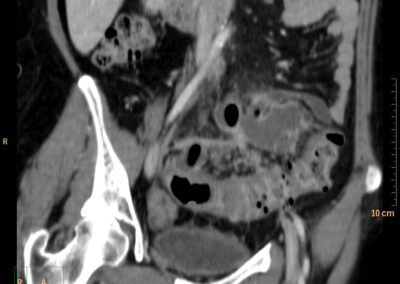

ΕΚΚΟΛΠΩΜΑΤΑ ΠΑΧΕΟΣ ΕΝΤΕΡΟΥ Posted by ΙΠΠΟΚΡΑΤΕΙΟ ΙΩΑΝΝΙΝΩΝ | Dec 16, 2020 | ΠΕΠΤΙΚΟ | 0 ΚΛΙΝΙΚΑ ΣΤΟΙΧΕΙΑ – ΙΣΤΟΡΙΚΟ υποτροπιάζοντες επαναλαμβανόμενοι πυρετοί κυρίως απογευματινές ώρες ΕΡΓΑΣΤΗΡΙΑΚΟΣ ΕΛΕΓΧΟΣ ΑΠΕΙΚΟΝΙΣΤΙΚΟΣ ΕΛΕΓΧΟΣ διακρίνονται τα αποστήματα στην ελάσσονα πύελο, καθώς και εκκολπώματα με εικόνα πάχυνσης του τοιχώματος του σιγμοειδούς ΣΥΖΗΤΗΣΗ